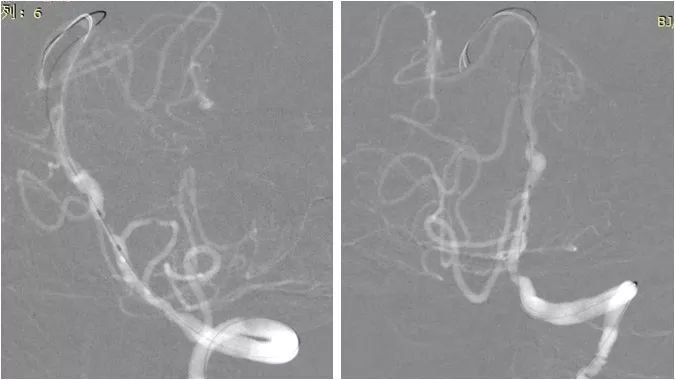

全麻下右股动脉入路,将6F导引导管至左椎动脉V2段。 造影显示左椎动脉V4段重度狭窄(图7)。

图7

路径图下将Transend微导丝(0.014”,300mm)送至右小脑上动脉远端,沿微导丝送入Gateway球囊(2.0mm×9mm)于狭窄处预扩张(图8)。

图8

扩张后撤出球囊,沿Transend微导丝送入Apollo球囊扩张支架(2.5mm x8mm ),命名压释放支架后造影,局部残余狭窄严重(图9)。

图9